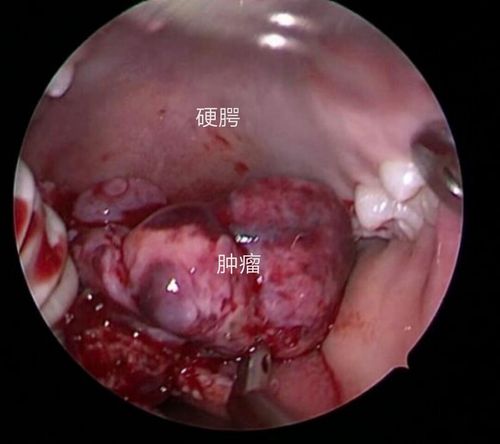

喉部肿物

喉部肿物,喉部感觉有异物

提示右侧声带肿物.

咽喉囊肿,多发性乳头肿瘤

医院耳鼻喉科成功开展支撑显微喉镜下二氧化碳激光微创治疗喉部肿瘤

nbi电子鼻咽喉镜__早期喉部肿瘤的透视镜

喉部肿瘤

良性喉肿物图

声带肿物图片